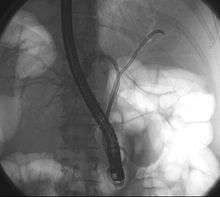

| Klatskin tumor during ERCP. In the left and right biliary system wires were placed. Both parts were injected through a tube with contrast. The lack of contrast in the area of the confluence is clearly visible. | |